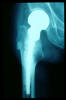

Fractura cuello fémur. Prótesis completa.

Fractura de fémur, prótesis parcial de cadera

Prótesis parcial de cadera

Prótesis de cadera.